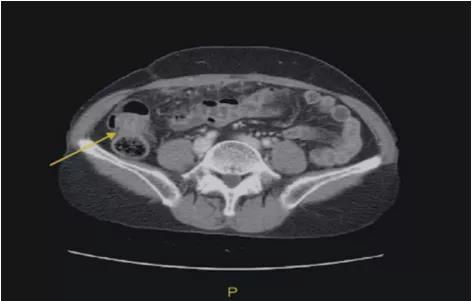

腹部盆腔CT:发现可疑为腹膜结核(TB)和左卵巢小囊性肿块。

增强的CT:网膜浸润,腹膜增厚,升结肠壁增厚。

图片来源:Seong Taek Mun

4、腹、盆腔CT有助于腹膜病变的鉴别疾病。但是,结核性腹膜炎和腹膜癌的表现相似,很难正确区分,特别是当卵巢大小正常,有腹膜脂肪浸润时,很难区分良性和恶性腹膜炎。

卵巢癌和结核腹膜炎的CT表现是可比较的,尽管卵巢包膜改变和卵巢实质衰减是与众不同的特征。